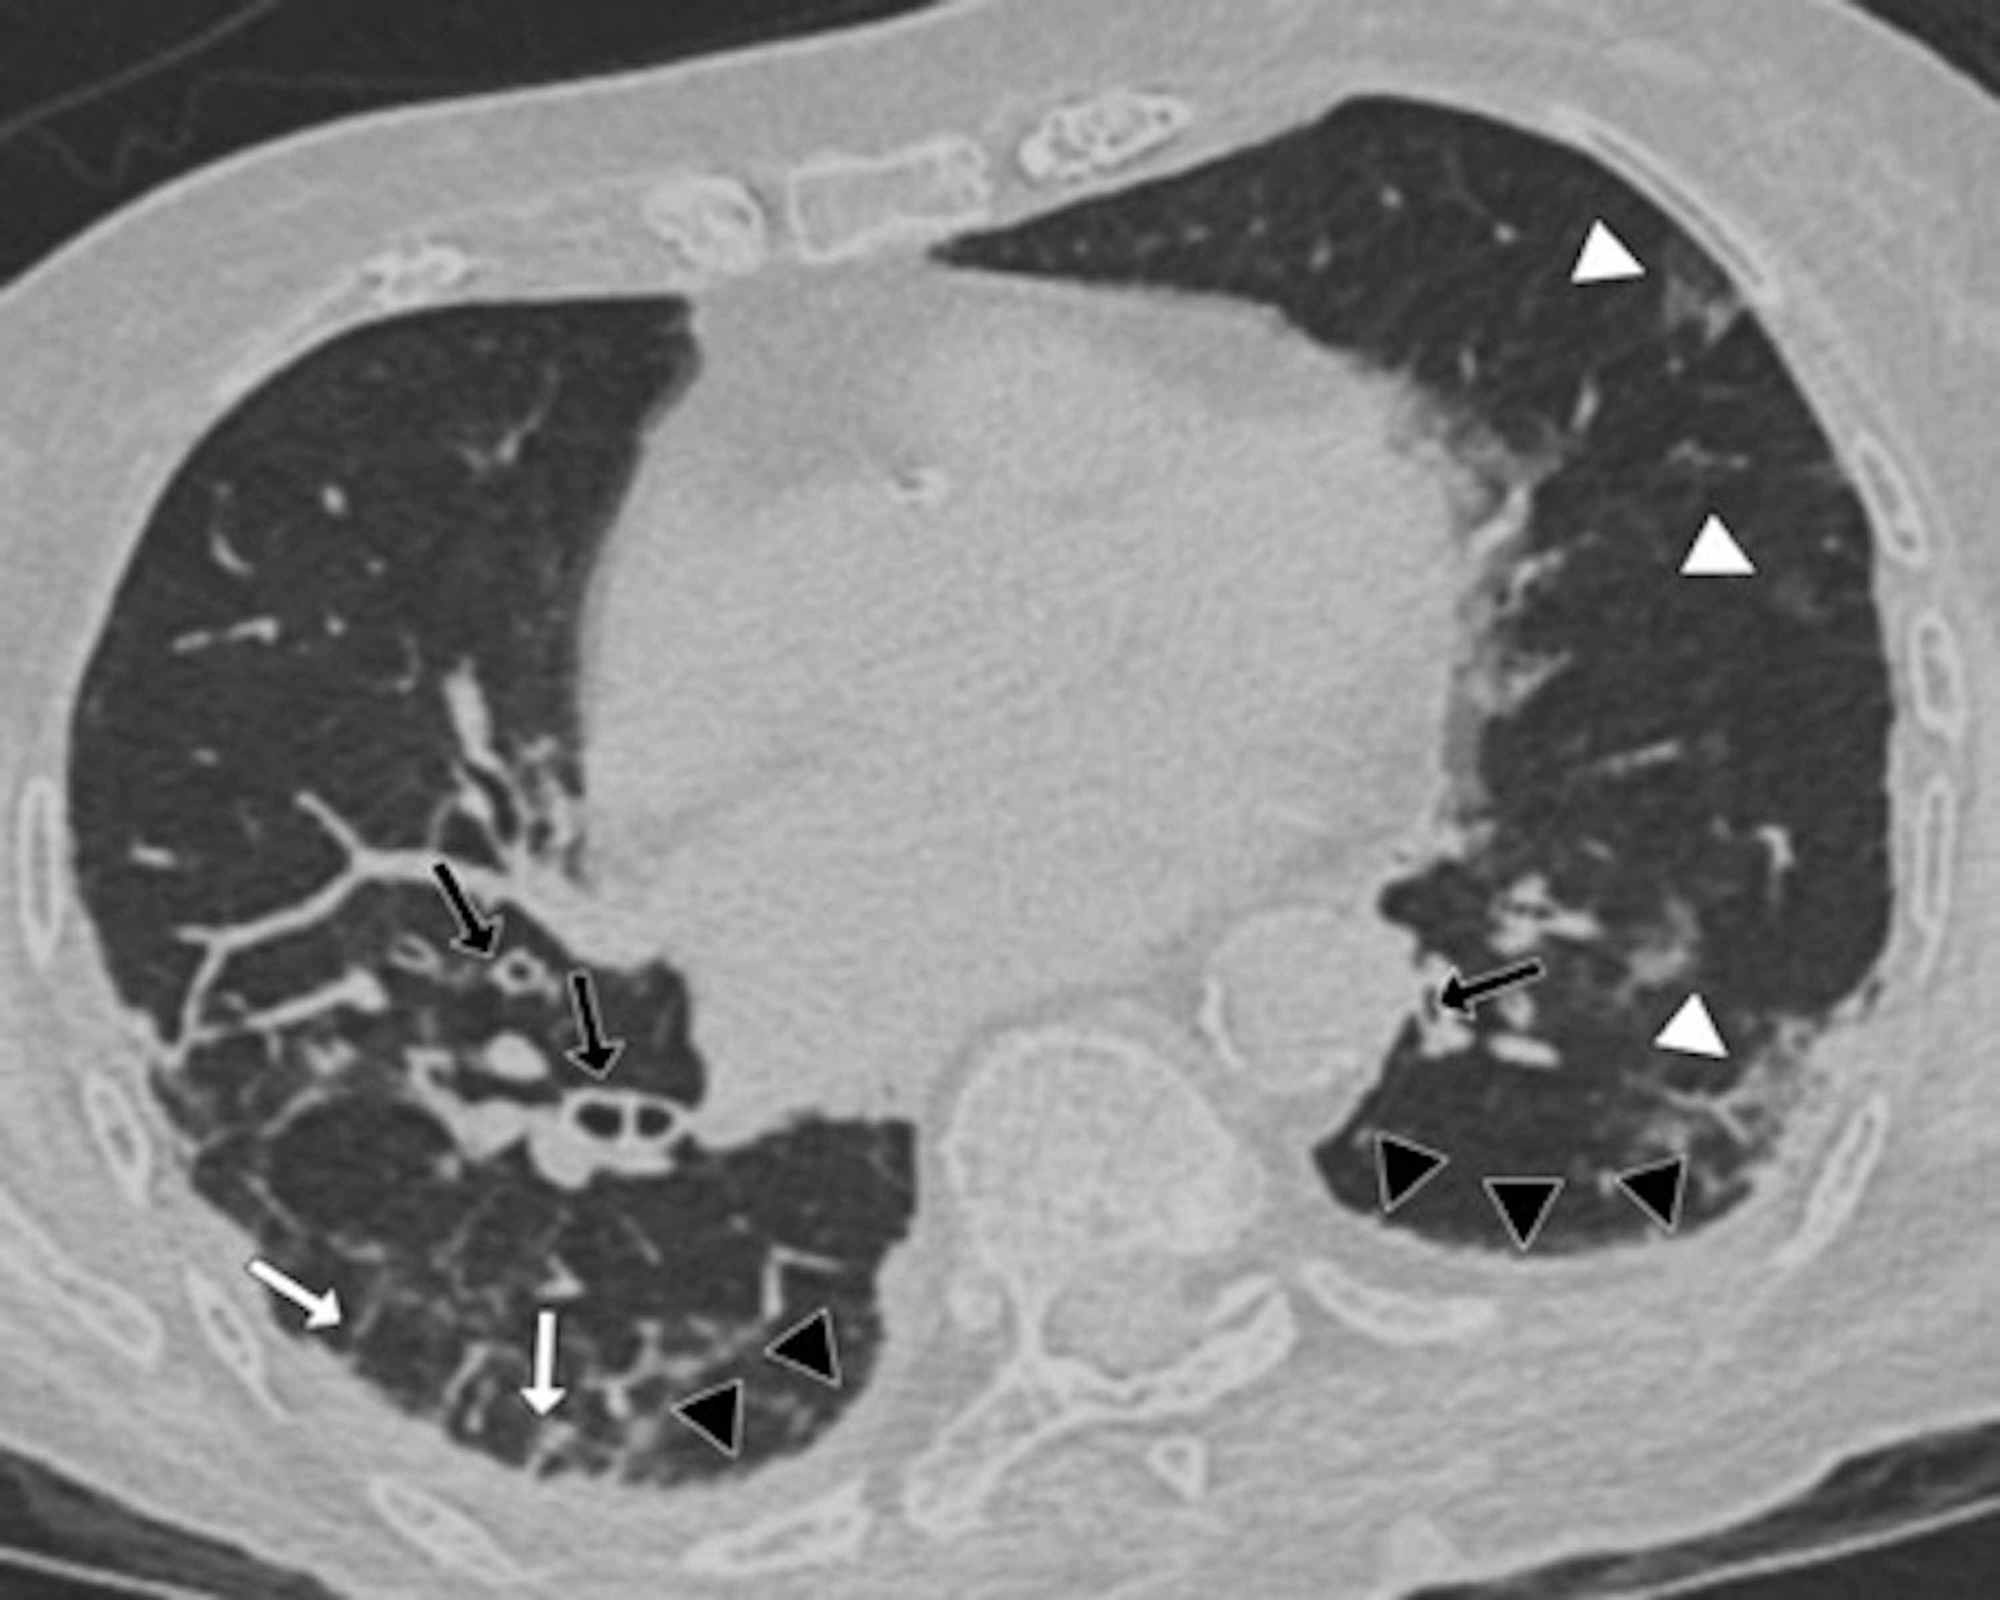

Two board-certified radiologists (E.P. and U.M., with 25 and five years of experience, respectively) reviewed the chest CT images on a picture archiving and communication system (PACS, Carestream Health, Inc, Rochester, NY). Chest CT images were evaluated with both mediastinal (width: 350 HU, level: 40 HU) and lung (width: 1500 HU, level: -500 HU) window level settings. The two radiologists identified pulmonary lesions based on their density, shape, and margin. The locations of the lung lesions were recorded as lobar, axial, anterior, and posterior. Axial locations were categorized as central (inner two-thirds of the lung) or peripheral (outer one-third of the lung). Each lung was divided by an axial line into anterior and posterior halves (Figures 2, 7). The densities of the patchy-confluent lesions were classified as pure GGO, pure consolidation, or mixed. Nodular lesion densities were classified as pure GGO, solid, or partly solid. Margins were classified as well-defined or ill-defined. As most of the lesions were patchy, confluent, and ill-defined margins, lesion sizes were not assessed. Instead, a visual severity score, which was slightly modified from Pan et al., ranging from 0 to 4 for each individual lobes was calculated. Each of the five lung lobes was visually scored on a scale of 0 to 4 as follows: 0: no involvement; 1: less than 25% involvement; 2: 25-50% involvement; 3: 50-75% involvement; and 4: 75-100% involvement.

In the CT images, GGO plus consolidation was observed bilaterally in all 18 (100%) patients. No pure GGO or pure consolidation was encountered in our cohort. The predominant shape was amorphous (72%). Lesions showed no specific lobar predilection, but most lesions were localized posteriorly and peripherally.

The distinctive CT features in our cohort are summarized in Table 3, including GGO and consolidative patchy mostly amorphous (72%) lesions, bilateral posterior and peripheral multi-lobar lung involvement, pleural effusions, subpleural fibrotic lines, subpleural sparing, vascular engorgement, occasional crazy paving, occasional mediastinal lymphadenopathy, pleural thickening, lack of cavitation, and absence of reverse halo (atoll) signs.

Subpleural sparing, which was observed in this patient cohort, has never been reported before, whereas mediastinal lymphadenopathy has been reported occasionally in the literature in English [11]. Focal vascular engorgement, septal thickening, and a subpleural fibrotic line were seen frequently in our cohort, with frequencies of 83%, 72%, and 61%, respectively.

Patients’ CT features are presented in detail in Figures 3, 4, 5, 6, 7, 8. A majority of cases (56%) had moderate severity scores. There was no correlation between the severity score and mortality, p=0.790 (Table 4).